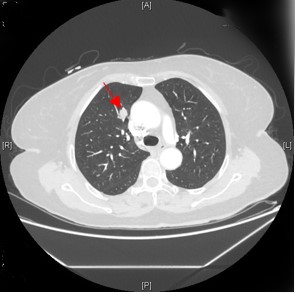

CT显示右肺肿瘤

同时,这次检查还意外地发现韩大妈右肺上有疑似恶性肿瘤,也需要手术治疗,当地医院犯了难。韩大妈最终来到清华大学附属北京清华长庚医院心脏外科进行治疗。主治医师崔晓征是韩大妈的首诊医师,了解她棘手的情况后,“您别着急,通过多学科联合,我们一定给您最适宜的治疗方案!”经与胸外科会诊,难题又出现了:如果先做心脏手术,就会延误时间,造成肺部肿瘤增大甚至转移;如果先做肿瘤切除,会因为心脏功能差而无法保证手术的开展。因此,如果两种手术一起进行,不但要求专科医生具有精湛的手术技术,而且还需要两科室的默契配合。